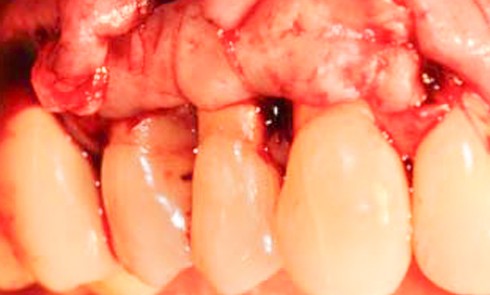

Les examens cliniques et radiographiques montrent une parodontite chronique généralisée (fig. 1a à m).

Nous décidons d’entreprendre une thérapeutique initiale parodontale classique dans tous les secteurs, y compris l’extraction de 24, un bridge de 45 à 48 avec 46 en pontique, un bridge complet de contention de 17 à 27 sur 11 piliers dentaires et une greffe épithélio-conjonctive sur 31. Cette dernière ne sera jamais réalisée. Le bridge maxillaire permettra de réduire le surplomb antérieur et d’améliorer le sourire de la patiente, ce qui constitue l’une de ses demandes.